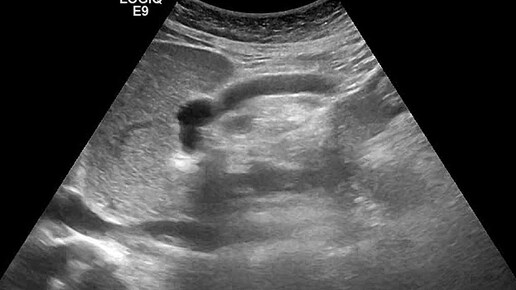

Видео к статье: "СЛУЧАЙ ДИАГНОСТИКИ СОЧЕТАННОЙ ПАТОЛОГИИ" Адрес: https://dzen.ru/a/aQRH94-8ajiog_3_

Ультразвуковые находки от врача УЗД Зорина Я.П.